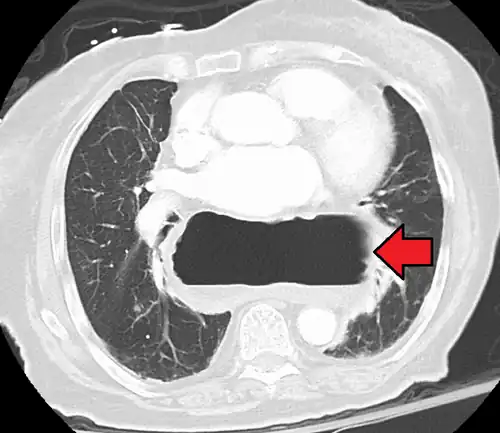

A hiatal hernia as seen on CT

A hiatal hernia as seen on CT -

A large hiatal hernia as seen on CT imaging

A large hiatal hernia as seen on CT imaging -

A large hiatal hernia as seen on CT imaging

A large hiatal hernia as seen on CT imaging -